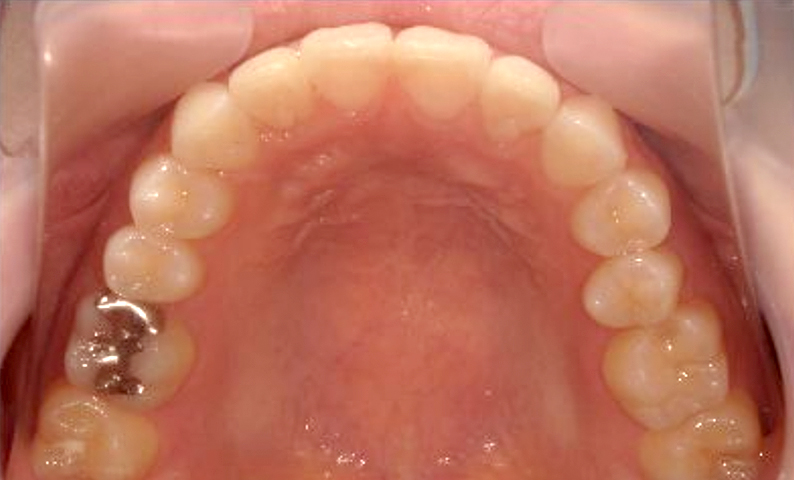

症例_025 上顎だけの部分矯正

治療期間:7ヶ月金額:30万円+税女性前歯のガタガタ上の前歯だけ

| Before | After |